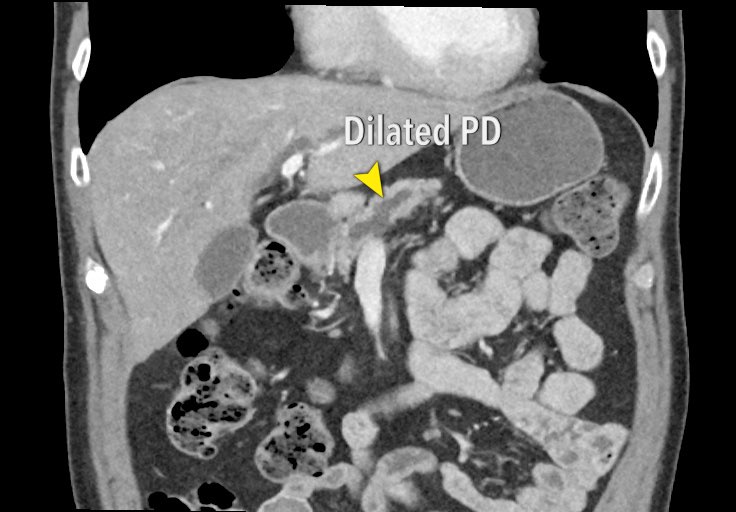

Pancreatic Cancer with Obstructed Pancreatic Duct Pancreas Case Imaging Studies Pancreatic Cancer The following tests may be used to rule out or diagnose pancreatic cancer. In pancreatic cancer, imaging plays an essential role in surveillance, diagnosis, resectability evaluation, and treatment response evaluation. Imaging tests might be done for many reasons both before and after a. Effective diagnostic imaging can improve prognosis for patients with pancreatic diseases such as pancreatitis, pancreatic cancer and. Imaging Studies Pancreatic Cancer.